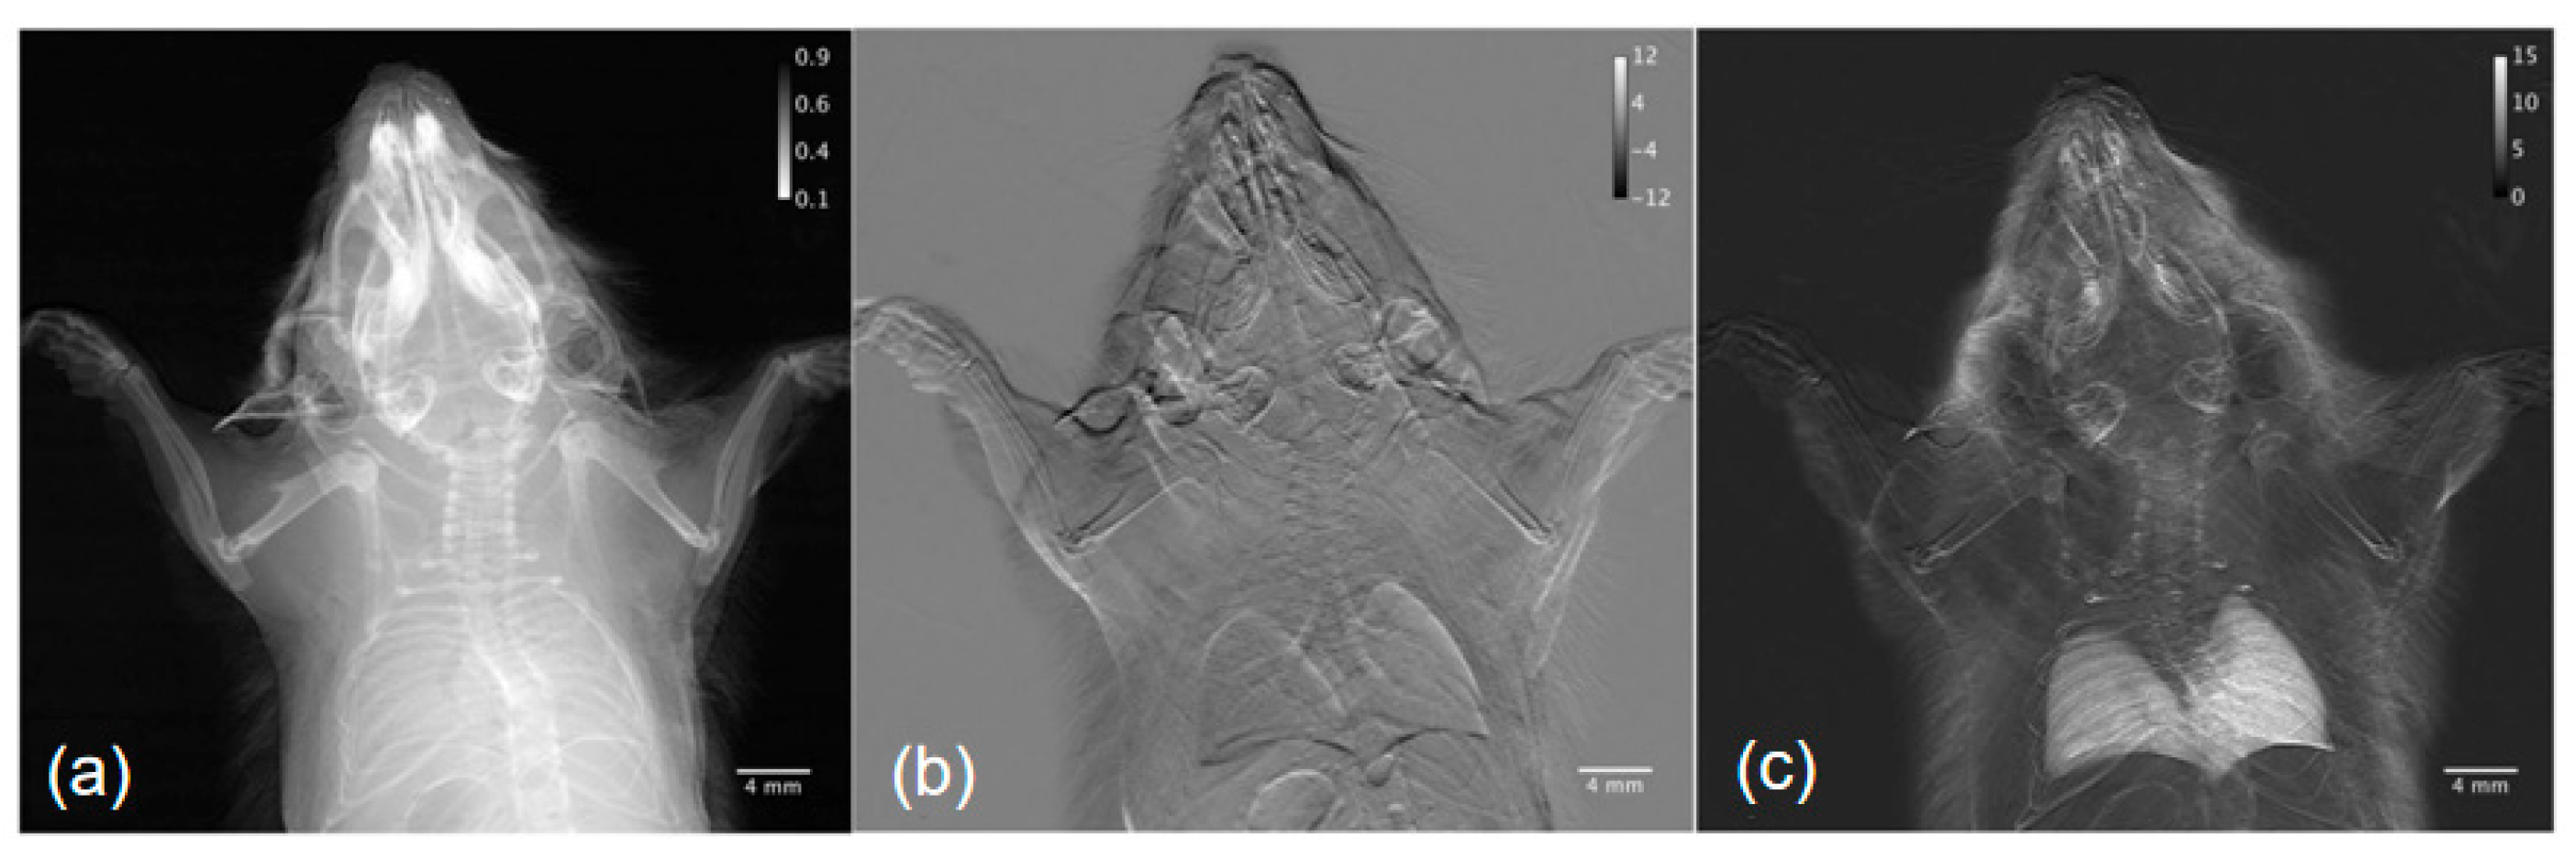

- Bech, M.; Tapfer, A.; Velroyen, A.; Yaroshenko, A.; Pauwels, B.; Hostens, J.; Bruyndonckx, P.; Sasov, A.; Pfeiffer, F. In-vivo dark-field and phase-contrast x-ray imaging. Sci. Rep. 2013, 3, 3209. [Google Scholar] [CrossRef]